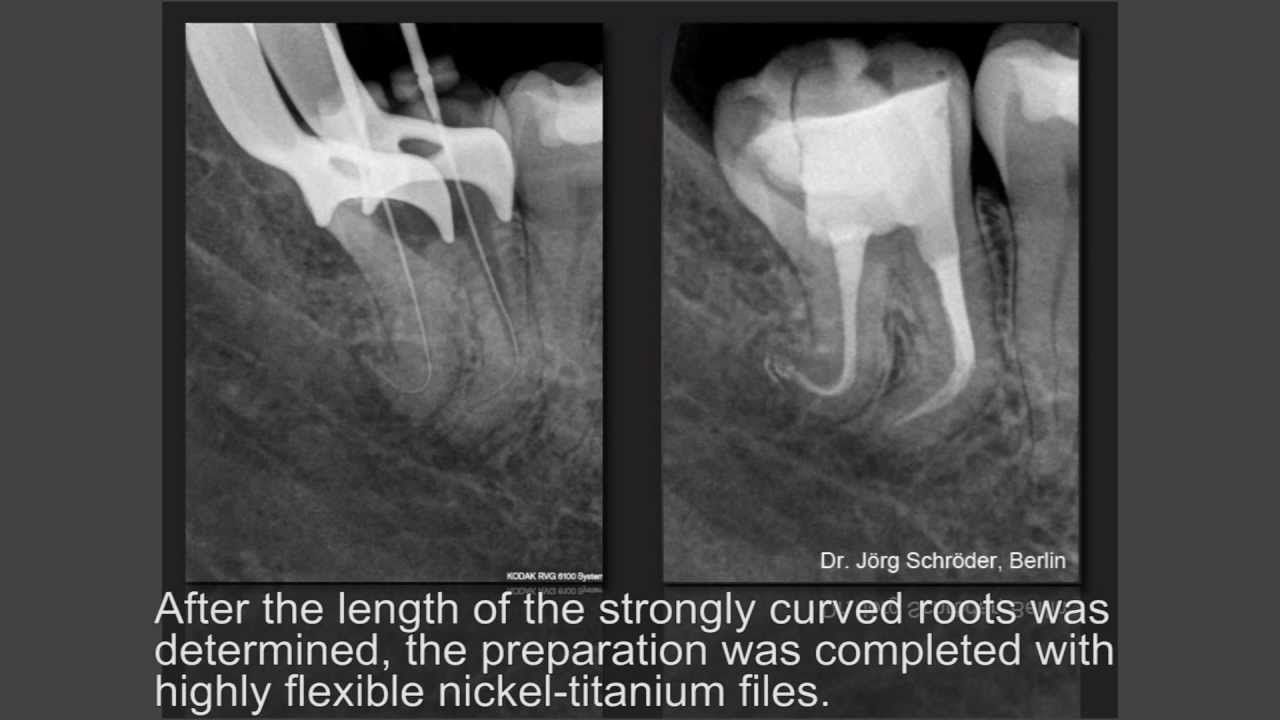

Cleaning and disinfection of root canals